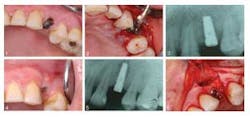

A 43-year-old female presenting with a symptomatic left, first premolar was a candidate for dental implant treatment and scheduled for an immediate implant placement following tooth extraction. After surgery she was prescribed antibiotics. She was seen three months later due to pain at the implant site, which revealed a sinus tract related to the implant. Additionally, there was a “soft spot” due to edema and bone loss. She was prescribed another course of antibiotics and returned in four days. At that time, a tetracycline paste was created and placed on the defect and around the implant for three minutes, then removed. In two months, a transitional crown was placed, with placement of the final six months later. At the subsequent one-, two-, six-month, one- and five-year appointments, no pain was reported and complete bone fill (see photo below) in to the previous lesion area was stable.